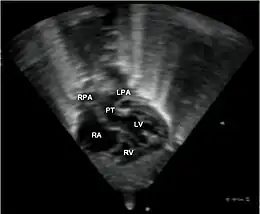

- le signe d'appel habituel est la perte du croisement des gros vaisseaux. Normalement, l'aorte et le tronc pulmonaire se croisent peu après leur sortie du cœur. Il est donc impossible de dérouler les deux vaisseaux sur un même plan de coupe. Quand l'aorte est vue longitudinalement, le tronc pulmonaire n'apparaît qu'en section transversale ("aorte en long, tronc pulmonaire en rond") et vice-versa. Dans la D-TGV simple, la plus fréquente, les vaisseaux ont un trajet parallèle et peuvent donc être visualisés longitudinalement simultanément.

- la confirmation est obtenue par l'analyse des gros vaisseaux et de leurs connexions aux ventricules. L'aorte est caractérisée par le fait qu'elle décrit une crosse, donne naissance aux vaisseaux à destinée céphalique et est le vaisseau qui monte le plus haut dans le thorax. Le tronc pulmonaire est caractérisé par sa bifurcation précoce en deux branches, les artères pulmonaires droite et gauche. Sur un cœur par ailleurs normal, le ventricule droit est situé en avant et à droite du ventricule gauche, le tronc pulmonaire est donc le vaisseau le plus antérieur. La TGV se caractérise par la position antérieure du vaisseau qui décrit la crosse et donne les vaisseaux céphaliques : l'aorte.

- la coupe parasternale gauche grand axe : elle montre que le vaisseau issu du ventricule gauche (le plus postérieur) se dirige anormalement vers l'arrière et se bifurque précocement. C'est donc le tronc pulmonaire et non l'aorte comme normalement ;

- les coupes sous costales qui montrent bien le trajet parallèle des gros vaisseaux et leur inversion.